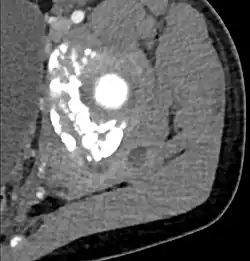

Transverse T2 magnetic resonance imaging section through the hip region showing abscess collection in a patient with pyomyositis.

Diagnostic methodDiagnostic method used for PM includes ultrasound, CT scan and MRI. Ultrasound can be helpful in showing muscular heterogeneity or a purulent collection but it is not useful during the first stage of the disease. CT scan can confirm the diagnosis before abscesses occur with enlargement of the involved muscles and hypodensity when abscess is present, terogenous attenuation and fluid collection with rim enhancement can be found. MRI is useful to assess PM and determine its localization and extension